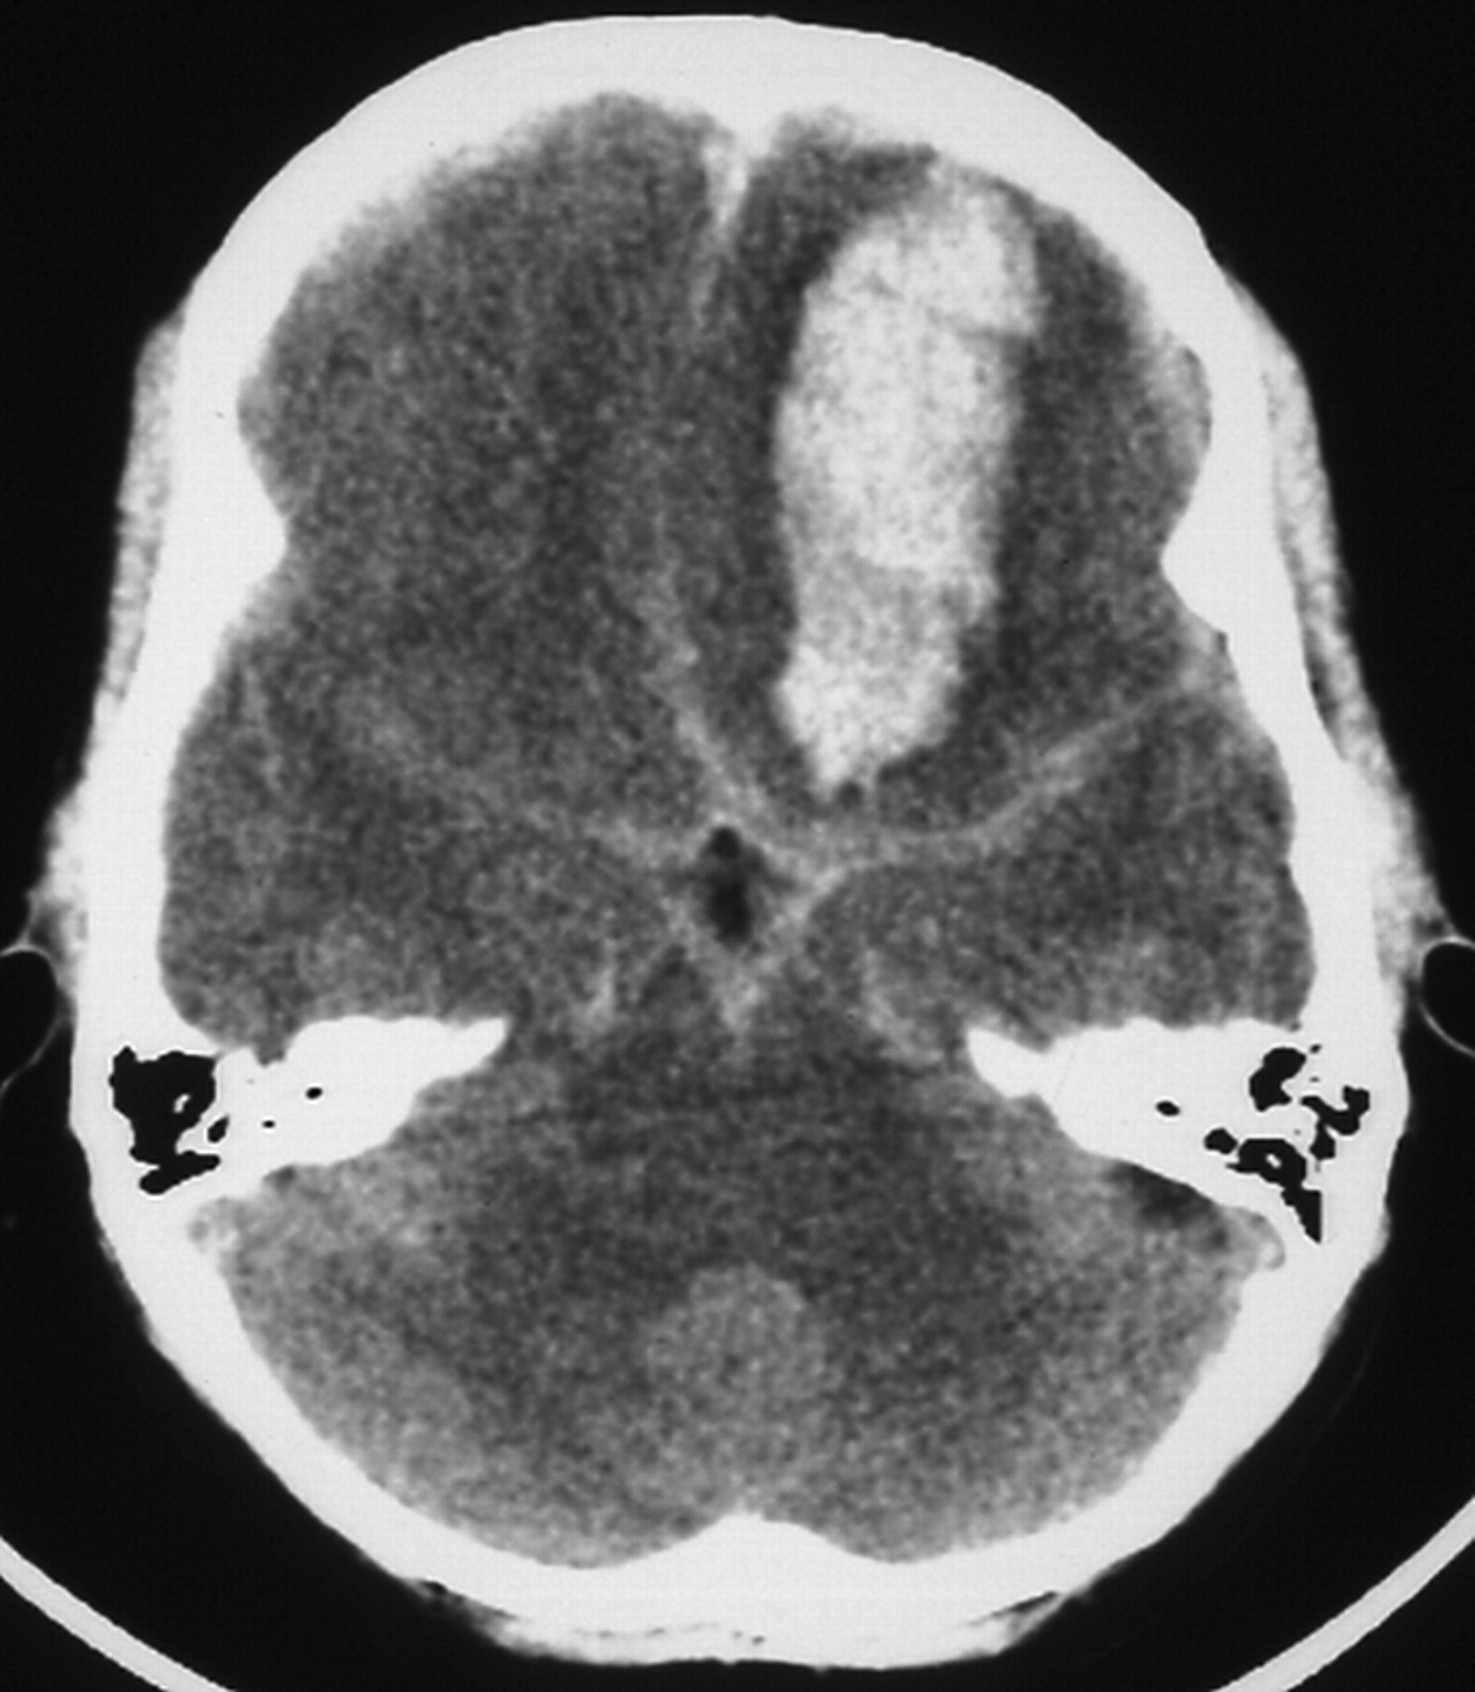

脑死亡后瞬态双边手指震颤

玛丽亚Leticia c Araullo,杰弗里。弗兰克,费尔南多·d·戈登伯格,阿克塞尔·j·Rosengart